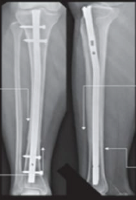

Volar locking plate fixation has been a favored surgical choice due to its capacity to provide secure fixation, preserve anatomical reduction, and promote early mobility, all of which are essential for good functional recovery [5]. The biomechanical benefit of locking plate designs, especially in osteoporotic bone, guarantees sufficient stability even in cases of comminuted or intra-articular fractures. Numerous studies have shown positive results with this method, but there is still a lot of variation in the results that have been recorded. This is due to the kind of fracture, the patient’s age, the timing of the surgery, and the rehabilitation that follows [6,7].

At the time of admittance, a detailed medical history and physical exam were done to find out how the event occurred, how healthy the individual was generally, and if they had any other problems that may be linked to it. The local examination focused on deformity, edema, pain, and functional impairment. We looked for compartment syndrome by checking the radial artery pulsations, capillary refill, and changes in sensation. At initially, a plaster slab below the elbow was employed to hold the individual immobile, and oral medications and non-steroidal anti-inflammatory drugs were given to help with the pain. Radiographic assessment included anteroposterior and lateral projections of both the injured and intact sides. Fractures were classified according to the Frykman and AO systems, evaluating radial length, inclination, palmar tilt, and articular step-off. Patients had a pre-anesthetic evaluation and then received open reduction and internal fixation with an anatomical volar locking plate, performed under regional or general anaesthesia. The duration between the injury and the operation was 3–12 days.